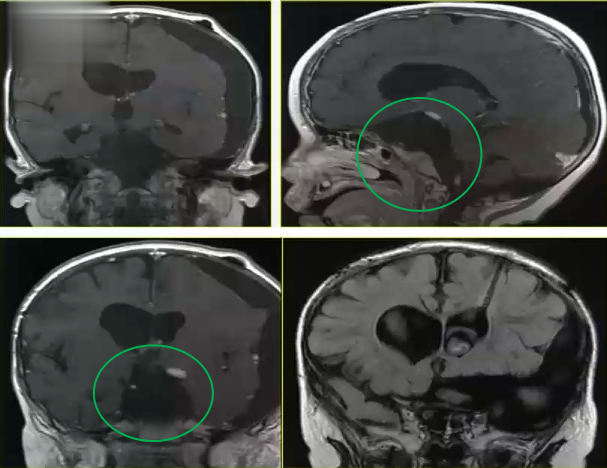

说起小禾的经历,要从视力异常说起。两岁的小禾原本有一双圆圆的黑亮眼睛,但确诊前出现了明显的视力下降,看不清东西,连颜色也分辨不清。家人带他去医院做了核磁共振检查,结果提示鞍区有肿瘤呈侵犯性生长,考虑为视路胶质瘤。有医生建议先尝试伽马刀治疗,但明确告知:可能无法保留视力。

家人不愿意让孩子以后都生活在黑暗中,所以没有选择伽马刀。医生为什么会建议先做伽马刀呢?原来视路胶质瘤如果不及时治疗,就有失明的风险。虽然这类肿瘤通常属于低级别胶质瘤,如果能够安全全切,不仅有可能保住视力,20年总体生存率还可以达到85%以上,但由于肿瘤起源于视神经并累及整个视路系统以及下丘脑等关键脑组织,手术的后遗症风险非常大,孩子一旦失明或许就再难恢复。如今神经外科的技术和设备已经发展到相当水平,视神经等疑难位置早已不是手术禁区,但视路胶质瘤的手术治疗至今仍未形成广泛共识。

那么决定做手术就一定是非明智之选吗?当然不是——小禾的视力就是被这样一台被多人说"不行"的手术保住的。回到那段焦虑的时光,小禾一家四处求医,最终前往德国找到了巴特朗菲教授。两岁幼童的大脑能够承受开颅手术那么大的压力吗?实际上,孩子的身心往往比成年人想象的要坚强得多。小禾克服了内心的恐惧,在巴教授的主刀下熬过了手术的几个小时,肿瘤被成功全切。